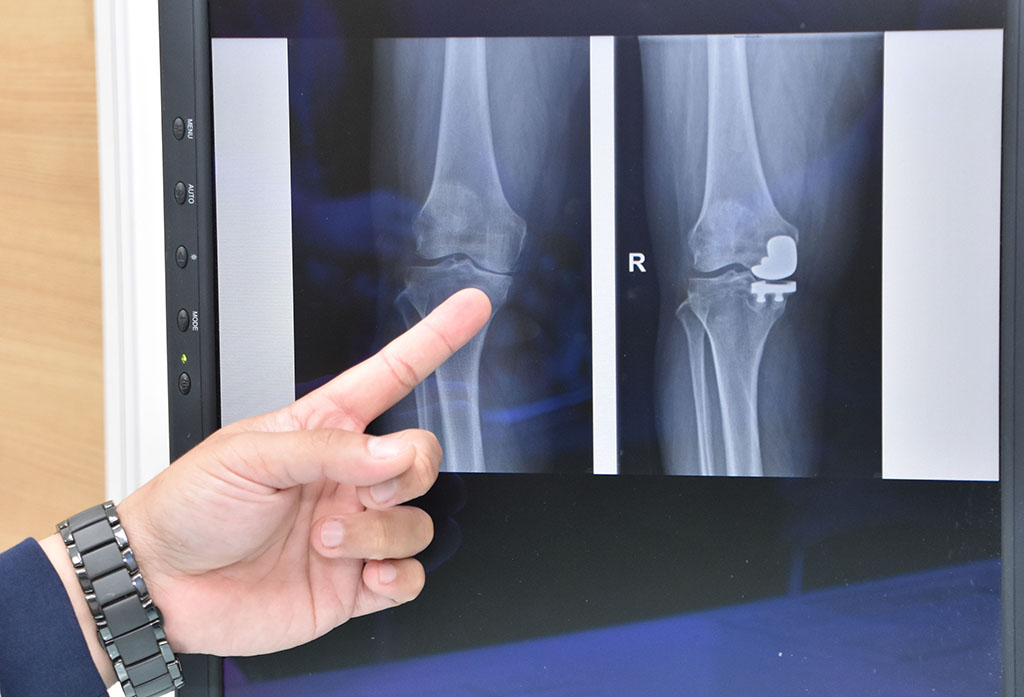

陳志鎧醫師表示,膝蓋退化並不一定要換整個膝蓋,可進行微創半套人工膝關節置換。

阿嬤內側膝關節退化,關節腔幾乎沒有空隙。

阿嬤經半套人工關節置換後,關節腔再度有了空間。